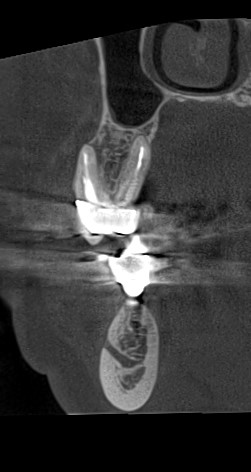

Клинические случаи в эндодонтии